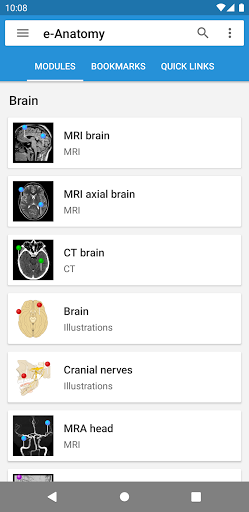

-Two new modules : Brain - TOF and Brain Angiography, Atlas of normal neurovascular anatomy of arteries of the brain on a cerebral angiogaphy.-The interface has been reworked.-A new tab named "QuickLinks" is available, dispatching modules in sections of the human body and allowing you to fast travel to the modules you are looking for.-Fixed small bugs.